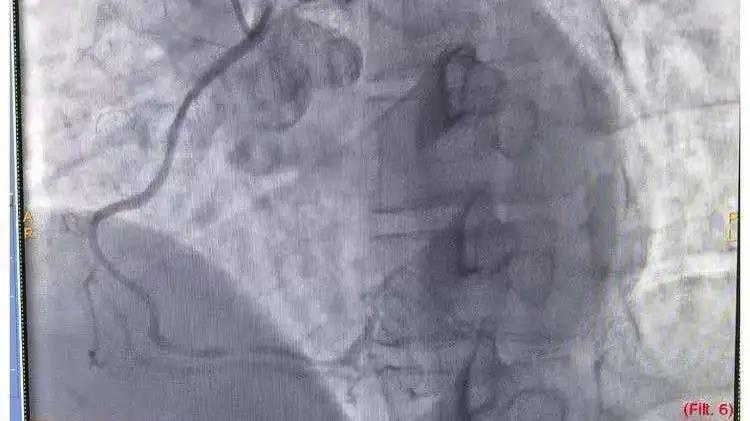

手术前